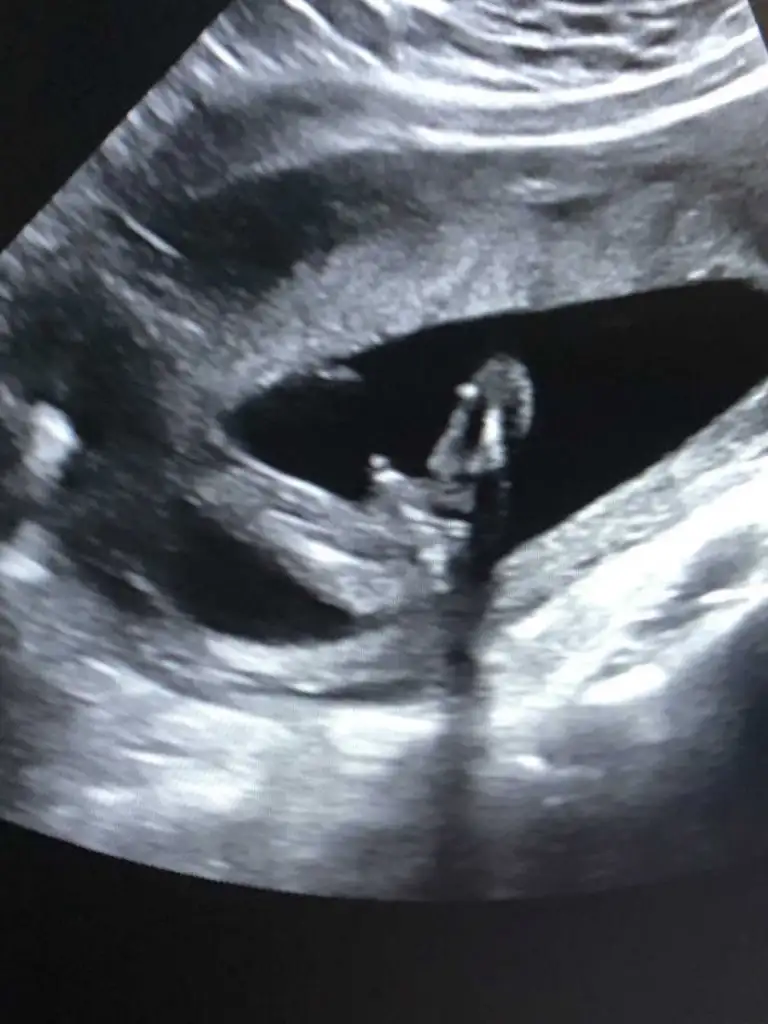

Bebeğimin cinsiyeti ...